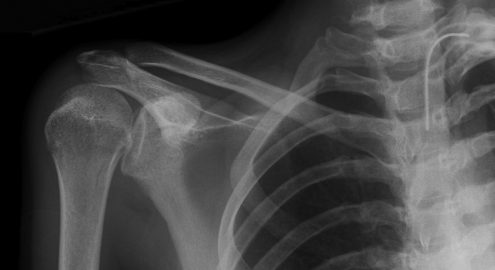

Рентгенография плечевых костей в 2-х проекциях (со снимком)

Рентгенологический метод исследования, который позволяет обнаружить наличие травматической патологии (вывихи и переломы), воспалительных изменений (артриты, остеоартрозы), новообразования (доброкачественные и злокачественные).

Рентгенография чаще всего назначается пациентам с острыми или хроническими болями в области плеча. При травмах болевой синдром будет максимально выражен и связан с недавно полученным ударом, падением, бытовой травмой. В этом случае рентген необходимо сделать в кратчайшие сроки.